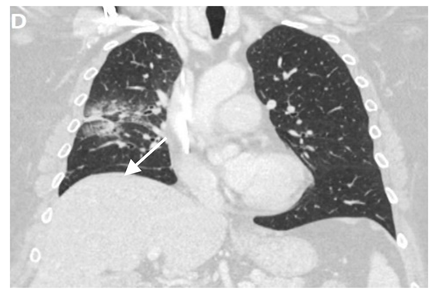

6.4.2. Chest CT-Scan

In the event of worsening symptoms after empirical antibiotics, Chest CT may provide more insights. Interestingly, the opacification lines in both X-ray and CT conform to radiation port rather than anatomical lines of lung structure, which could be diagnostic. Identified progression outside the lung field might suggest immune-mediated lymphocytic alveolitis [72]. Various stages of presentation provide different imaging outlooks (Table 3).

During the acute exudative stage, features of ground-glass attenuation or homogeneous consolidation may be noticed. A patchy consolidation that confirms the irradiation portal is also suggestive of the early phase. A discrete consolidation that conforms to the shape of the irradiation portal is proliferative changes of irradiation [71].

A chronic fibrosis stage with features of parenchymal distortion, traction bronchiectasis, and pleural thickening resulting in volume loss and irreversible changes are noticed. Refer to Table 2.